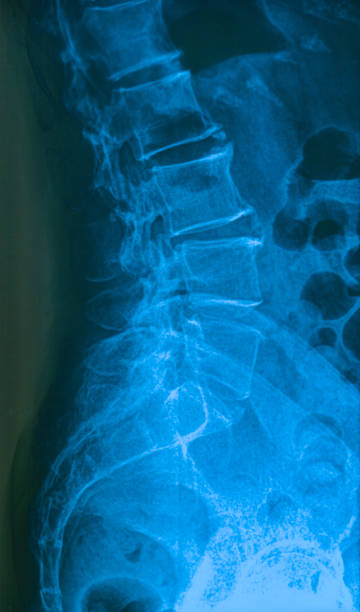

골반은 복부 하단에 위치하고 있는데 양쪽의 2개 볼기뼈와 후단부의 천골(엉치뼈)와 미골(꼬리뼈)로 구성되어 있으며 척추 부분과 하지를 연결하여 체중을 지탱하며 각종 내장과 자궁, 난소, 방광 등 주요 장기를 외부 충격에서 보호할 수 있습니다.

처장관절은 천골(엉치뼈), 장골(엉덩이뼈)가 만나는 부위로 외부 충격 혹은 골반이 힘을 주며 불편한 자세로 일어나거나 한쪽으로 체중이 쏠리는 잘못된 자세로 인하여 천장관절 주변으로 조직이나 인대 등에서 통증을 유발하는데 심할 경우 계단 오르내리는 것 자체도 어려워 질 수 있습니다.